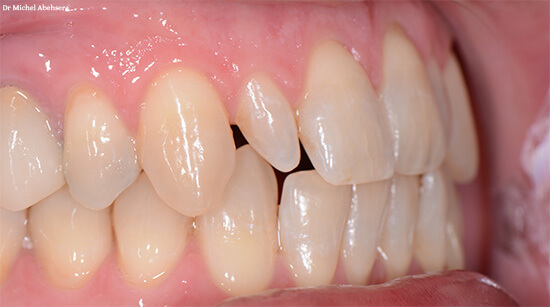

Les anomalies de position et d’éruption

Ces anomalies concernent la localisation finale de la dent dans l’arcade dentaire.

- Inclusion dentaire : la dent reste en position intra-osseuse après sa date d’éruption physiologique, sans contact avec le milieu buccal. Elle touche le plus souvent les canines maxillaires.

- Dent enclavée : la dent communique avec le milieu buccal, au moins par une cuspide, mais ne peut pas émerger complètement.